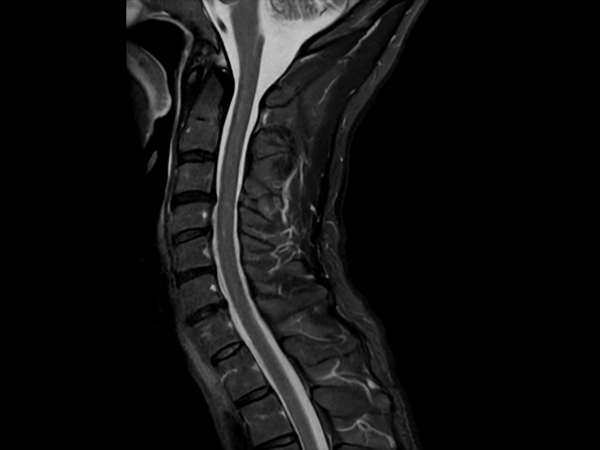

High quality Cervical Spine imaging with SmartSpeed Precise